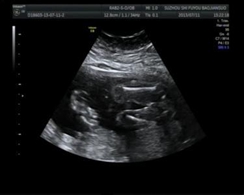

醫(yī)學(xué)影像學(xué)可以作為一種醫(yī)療輔助手段用于診斷和治療,也可彩超

彩超(3張)

以作為一種科研手段用于生命科學(xué)的研究中。診斷主要包括透視、放射線片、CT、MRI、超聲、數(shù)字減影、血管造影等。治療主要應(yīng)用為介入治療、放療等方面。